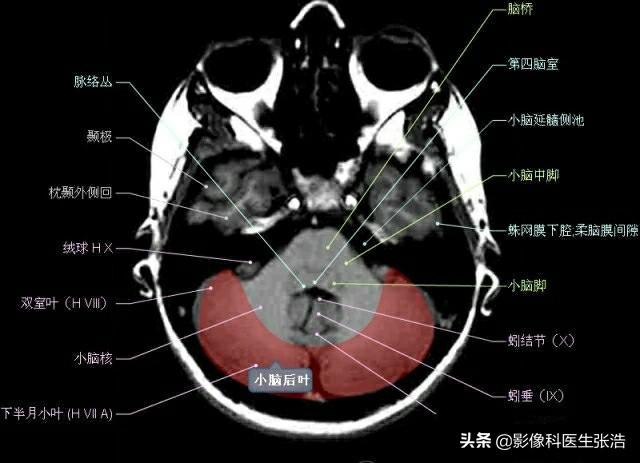

核磁共振(MRI)是一種利用磁場和射頻脈沖來生成身體內部結構的詳細圖像的非侵入性檢查技術,頭部核磁共振主要用于檢查腦部疾病、神經系統(tǒng)問題以及血管狀況等,這項檢查對于疾病的早期發(fā)現(xiàn)和治療具有非常重要的意義。